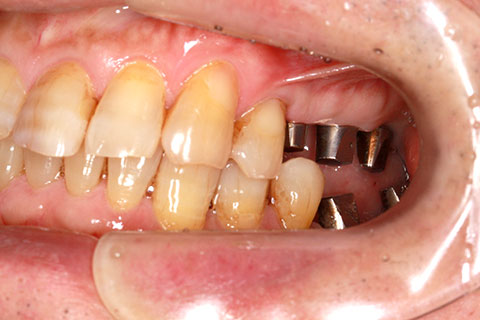

• 症例2

治療前

インプラント埋入時

治療後

年齢・性別

57歳男性

治療期間

3ヶ月

抜歯

なし

治療費

154万円

備考

左上5.6.7 及び左下6.7欠損

治療内容

左上5.6.7と左下6.7欠損部にインプラント埋入

施術の副作用(リスク)

オペによる知覚障害。インプラントによる歯肉炎。インプラント脱落。